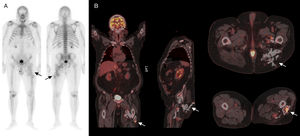

A) Gammagrafía ósea de cuerpo completo con 99mTc-hidroxi-metilen-difosfato en proyecciones anterior y posterior en las que se observa un incremento patológico e irregular de la actividad osteoblástica en el tercio medio y proximal de muslo izquierdo, con captación del trazador en tejidos blandos adyacentes y alteración en la morfología ósea normal (flechas). B) Planos coronal, sagital y axiales de estudio 18F-FDG PET/CT en el que se observan múltiples acúmulos patológicos del radiotrazador que se distribuyen desde planos postero-inferiores de la nalga izquierda hasta tercio medio del muslo ipsolateral (flechas).

Presentamos a un varón de 66 años, con antecedente de fibrohematoma, intervenido en el muslo izquierdo, en seguimiento por traumatología. Se realizó gammagrafía ósea tras administración de 815 MBq de 99mTc-hidroxi-metilen-difosfato, observándose un incremento patológico de la actividad osteoblástica en partes blandas del tercio medio y proximal de muslo izquierdo hasta la cadera izquierda, con captación del trazador en zona de tejidos blandos adyacentes y alteración en la morfología ósea normal (fig. 1 A) compatible con miositis osificante. Tras años de evolución, y en el contexto clínico de lesión indicativa de neoplasia pulmonar, se realizó PET/TC tras administración de 370 MBq de 18-fluordesoxiglucosa (18F-FDG), en la que se observaron varios acúmulos patológicos del radiotrazador que se distribuyen por los planos postero-inferiores de la nalga izquierda hasta el tercio medio del muslo ipsolateral (fig. 1 B), con un valor de captación máximo estandarizada (SUV) máximo de 9,1 en relación con lesión de morfología muy abigarrada, con zonas calcificadas, hipodensas y de tejidos blandos. Estos hallazgos se corresponderían con una miositis osificante de localización estrictamente inferior a la punta del trocánter mayor3. A diferencia de las calcificaciones metastásicas, que se asocian a una alteración del metabolismo fosfo-cálcico, la miositis osificante puede aparecer como complicación de lesiones musculares con hematoma secundario a inflamación de la fascia tras una lesión neurológica, cirugía, traumatismo o quemadura4.